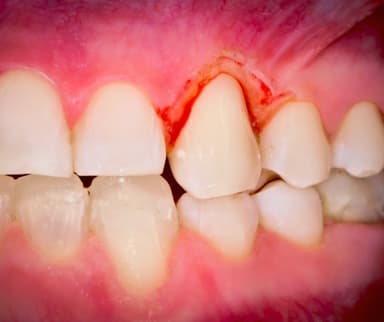

Viêm nướu là tình trạng viêm nhiễm của nướu, gây ra các triệu chứng như sưng đỏ, chảy máu chân răng, hơi thở có mùi hôi, v.v. Đây là bệnh lý rất dễ xảy ra. Đồng thời, khi không được điều trị kịp thời, người bị viêm nướu có thể phải đối diện với những biến chứng nguy hiểm như viêm nha chu, ảnh hưởng đến sức khỏe răng miệng và toàn thân.

– Nướu sưng đỏ

– Tình trạng chảy máu chân răng, thường dễ nhận thấy nhất khi khi đánh răng hoặc dùng chỉ nha khoa

1.3. Ảnh hưởng do viêm nướu

Là một trong những bệnh lý răng miệng phổ biến, nhưng viêm nướu răng thường không được quan tâm đúng cách. Rất nhiều người thường lơ là, phớt lờ bệnh và nghĩ tình trạng này sẽ tự khỏi, chỉ đến khi thấy tình trạng viêm nướu nghiêm trọng hơn mới đi mua thuốc hoặc đi khám. Trong khi đó, các bác sĩ Răng Hàm Mặt của TCI khuyến cáo: Nếu không được điều trị kịp thời, người bệnh viêm nướu có thể gặp biến chứng viêm nha chu, gây tổn thương nghiêm trọng đến mô nướu và xương hàm, thậm chí dẫn đến mất răng.